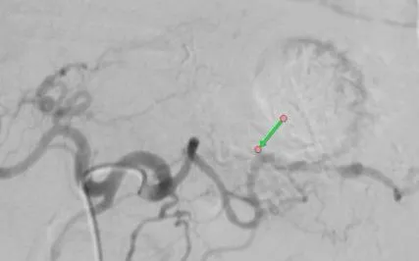

Cầm máu thành công ca ung thư dạ dày biến chứng

Sức khỏe

-

Bệnh viện Đa khoa Thủ Đức (TP Hồ Chí Minh) vừa can thiệp nội mạch cầm máu thành công cho bệnh nhân ung thư dạ dày giai đoạn muộn bị xuất huyết ồ ạt, nguy cơ sốc mất máu.